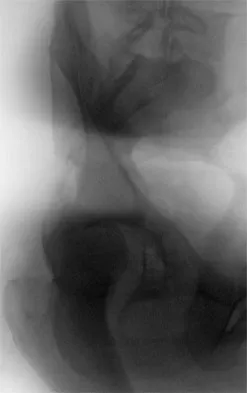

Which of the following choices best describes the fracture pattern shown in Figures 2a through 2c?

Explanation

The fracture pattern shown in the radiographs is a fracture of the posterior column. The only line interrupted on the AP pelvis is the ilioischial line. The obturator oblique view shows that the iliopectineal line is intact as is the outline of the posterior wall. The iliac oblique view shows an interruption of the ilioischial line and an intact anterior wall. Therefore, this fracture is a fracture of the posterior column. Letournel E, Judet R: Fractures of the Acetabulum, ed 2. Berlin, Germany, Springer Verlag, 1993.